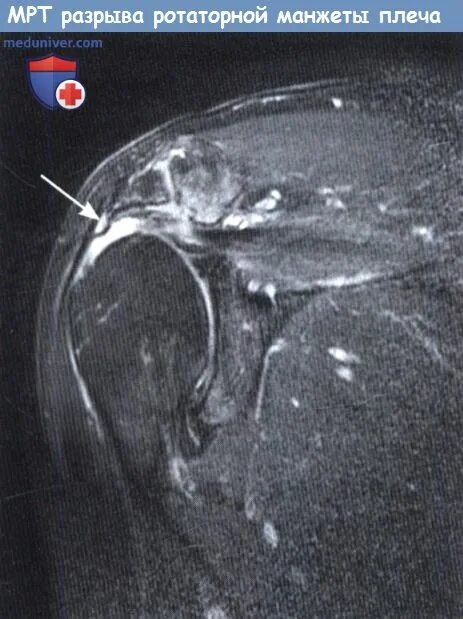

Повреждение вращательной манжеты мкб